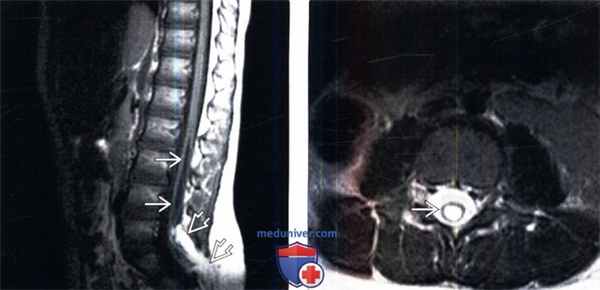

(Слева) Сагиттальный срез, Т1-ВИ (синдром фиксированного спинного мозга): низкое расположение и кистозная трансформация спинного мозга, дистальный конец которого связан с липомиеломенингоцеле крестцовой области.

(Справа) На аксиальном Т2-ВИ (крестцовое липомиеломенингоцеле при синдроме фиксированного спинного мозга) отмечается дилятация центрального канала спинного мозга, интенсивность сигнала соответствует СМЖ, что характерно для гидросирингомиелии.